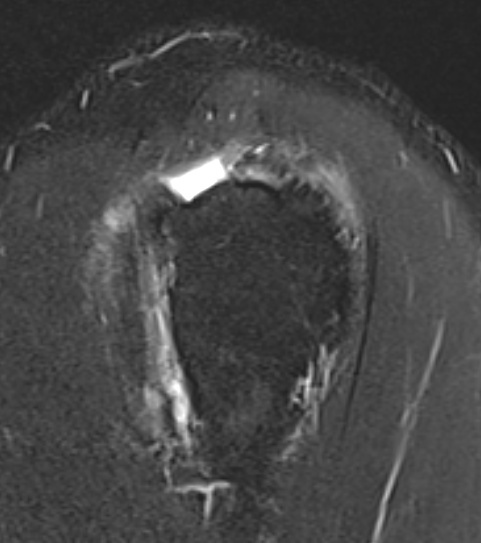

Subscapularis tears

Supraspinatus atrophy

Tangent sign

- sagittal MRI

- line connecting superior coracoid and superior border scapular spine

- if supraspinatus muscle is below line, there is significant atrophy

- positive tangent sign / significant atrophy associated with larger tears / irrepairable tears

Negative tangent / no atrophy Positive tangent / significant supraspinatus atrophy